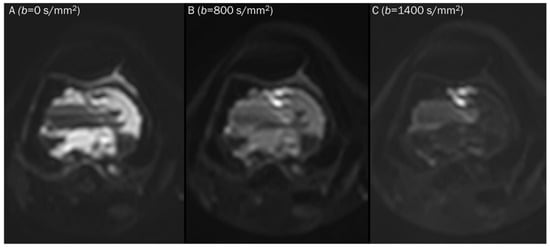

7.2. Hematoma

| Stage | Component | Age | T1WI | T2WI | DWI | ADC Map |

|---|---|---|---|---|---|---|

| Hyperacute | Intracellular oxyhemoglobin | <6 h | Iso | Hyper | Hyper | Hypo |

| Acute | Intracellular deoxyhemoglobin | 6–72 h | Iso | Hypo | Hypo | Hypo |

| Early subacute | Intracellular methemoglobin | 3–7 d | Hyper | Hypo | Hypo | Hypo |

| Late subacute | Extracellular methemoglobin | 1–4 w | Hyper | Hyper | Hyper | Hypo-to-iso |

| Chronic | Hemosiderin | >1 m | Hypo | Hypo | Hypo | Hypo |

| Hematoma | ||

| Acute stage | T2 black-out | Deoxyhemoglobin |

| Early subacute stage | T2 black-out | Intracellular methemoglobin |

| Chronic stage | T2 black-out | Hemosiderin |